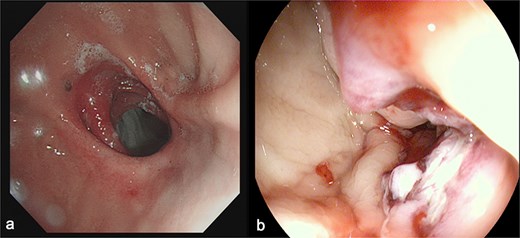

(a) Depicts the preoperative gastroscopy and (b) shows the postoperative gastroscopy.

Endoscopy/imaging: Patent GGA without stenosis/leakage (Fig. 4). Normal antral peristalsis and pyloric function (Fig. 5).